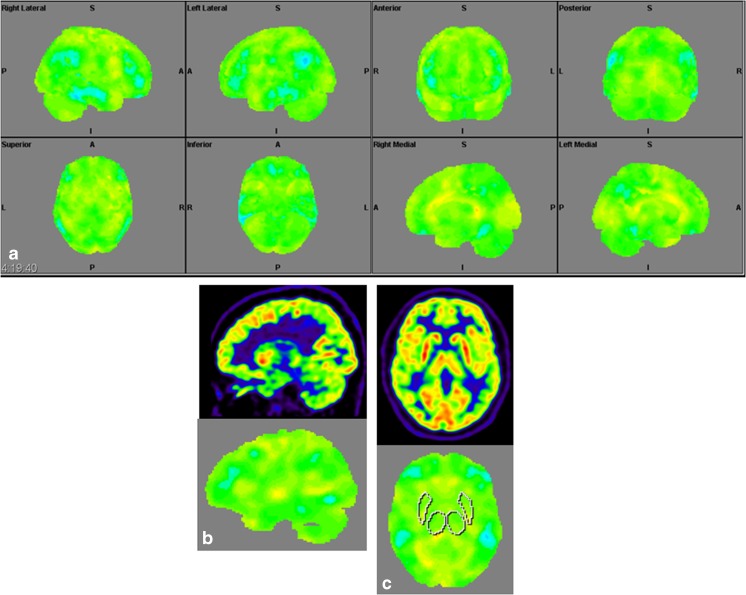

Structural Brain Imaging and [18F] FDG PET

The imaging data are summarized in Table 1 and are shown in Figs. 2, 3, 4, 5, 6, 7, and 8. Brain MRI revealed atrophy of the vermis and supratentorial white matter hyperintensities (WMH) in patients III:1 and III:2 and to a lesser degree in the index case (Figs. 2, 3, and 5). These WMH were particularly widespread in III:1 (Fig. 2). The index case was not affected by any other comorbidity usually associated with WMH, suggesting that these abnormalities may be an underlying feature of SCA19/22. WMH were not evident in the youngest patient (V:1). [18F] FDG PET revealed hypometabolism in the entire cerebellum, thalamus, prefrontal cortex (PFC), and parietal regions of the index case (IV:1) (Fig. 6). Her mother had reduced glucose metabolism not only in the PFC but also in the vermis as wells as in the motor and temporal cortex (Fig. 4). The youngest patient (V:1) had hypometabolism in the PFC, parietal, and inferior temporal regions but surprisingly not in the cerebellum (Fig. 8). In the latter structure, atrophy of the vermis was evident (Fig. 7).

Fig. 4.

Surface projections (3DSSP) of brain [18F] FDG PET findings for patient III:2. a Widespread hypometabolism in the prefrontal cortex and some areas of the motor and temporal cortices is evident. Metabolism is also reduced in the vermis but normal in the cerebellar hemispheres. b Midsagittal image shows reduced FDG uptake in the vermis (upper case) as compared to the reference values in VOI templates (lower case). c Coronal image shows normal FDG uptake in the putamen (upper case) as compared to the reference values (lower case)

Fig. 6.

Surface projections (3DSSP) of brain [18F] FDG PET findings for patient IV:1. a Metabolism is reduced in the prefrontal and parietal cortex as well as in the entire cerebellum. b Midsagittal image shows reduced FDG uptake in the cerebellum (upper case) as compared to the reference values in the VOI templates (lower case). c A similar abnormality is evident in the thalami on the coronal image (upper case) as compared to the reference values (lower case), FDG uptake in the putamen is otherwise normal

Fig. 8.

Surface projections (3DSSP) of brain [18F] FDG PET findings for patient V:1. a Displays hypometabolism in the prefrontal cortex, lateral temporal cortex, and in some areas of the parietal cortex. b Metabolism in the cerebellum is normal on this midsagittal image (upper case). c FDG uptake is also normal in the basal ganglia and thalami on the coronal image (upper case); reference values in VOI templates are displayed in the lower cases of B and C